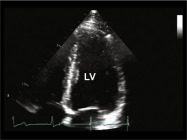

| 2.2. Mặt cắt trục dài cạnh ức khu trú vào thất trái

|

||||||||

|

|

Cửa sổ siêu âm cạnh ức

Mặt cắt trục dài cạnh ức Đầu dò đặt tại bờ trái xương ức với marker hướng lên vai phải của bệnh nhân. Chùm siêu âm đặt vuông góc với thất trái. |

Nhĩ trái (LA)

Van hai lá (MV) Thất trái (LV) Đường ra thất trái (LVOT) Van động mạch chủ (AV) Vách liên thất (IVS) Thất phải (RV) |

|||||